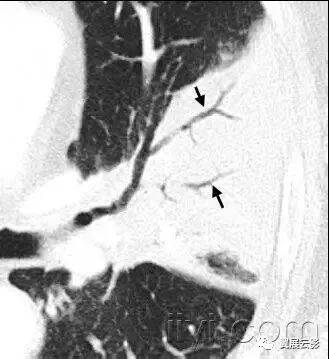

七十一、牵拉性支气管扩张或者细支气管扩张

CT:牵拉性支气管扩张和细支气管扩张是由于周围肺纤维化牵拉导致的支气管和细支气管的不规则扩张。扩张的气道可以如图所示,可以是囊状(支气管)或者是小囊状(细支气管)。多发囊样气道变形与单纯性纤维化所致蜂窝征难以鉴别。